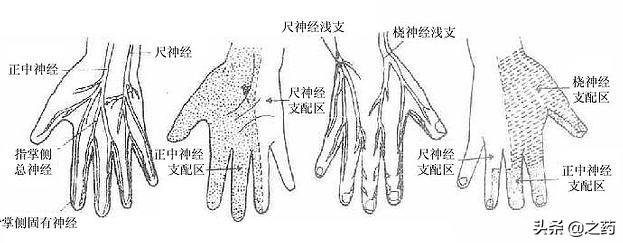

指の知覚神経は頸髄から神経根に分かれ、頸部腋窩で腕神経叢を形成し、上腕と前腕を通って橈骨神経、正中神経、尺骨神経となり、手と指に分布する末梢神経となる。

尺骨神経の損傷。同じ側の小指と薬指のしびれや痛み、一部の指の運動障害を引き起こすことがある。肘の後方にある尺骨神経の溝は、損傷や圧迫を受けやすい。

正中神経損傷: 前腕と上腕の正中神経は、外傷、腫瘍、圧迫などにより、手掌面、親指、人差し指、中指にしびれや痛みを生じる。手首は、手根管症候群と呼ばれる損傷や圧迫に対して最も脆弱であり、治療原則は以前と同じです。

橈骨神経の損傷橈骨神経は上腕側面の中央から下部にかけて傷害を受けやすく、親指と人差し指の甲のしびれや痛み、指と手首の下垂を伴う。

頚髄神経根を分割し、頸部に形成する。腕神経叢分ける橈骨神経、正中神経、尺骨神経経絡は上腕と前腕を等距離に通過し、最終的に頚椎となる。末梢神経手と指に分布している。そのため、指先のしびれは必ず上記の神経に問題がある。

2.橈骨神経、正中神経、尺骨神経の損傷

上腕外側面の中央下部にある橈骨神経は、次のような影響を受ける。圧迫、外傷、腫瘍などにつながる可能性がある。親指と人差し指の裏側のしびれと痛み、指と手首の下垂。.正中神経が損傷すると、次のようなことが起こる。手のひら、親指、人差し指、中指のしびれと痛み。尺骨神経の損傷はその結果である。尺骨神経の損傷は、その後、次のような結果をもたらす。同側の小指と薬指にしびれと痛みがあり、一部の指の動きが悪くなる。

手の指はさまざまな神経に支配されている。

親指、人差し指、中指の半分は正中神経に支配されている。

小指、薬指、中指の残り半分は尺骨神経に支配されている。

この2本の神経が圧迫されると、指のしびれが起こることがある。

手根管症候群と呼ばれる正中神経の圧迫の場合、親指側の3本の指のしびれや、親指側の手掌面の筋萎縮が起こることもある。

尺骨神経に巻き込まれた場合は、手首尺骨神経巻き込み症と呼ばれ、通常、小指側の3本の指の手掌面にしびれ、小指側の手掌面の筋萎縮まで伴う。